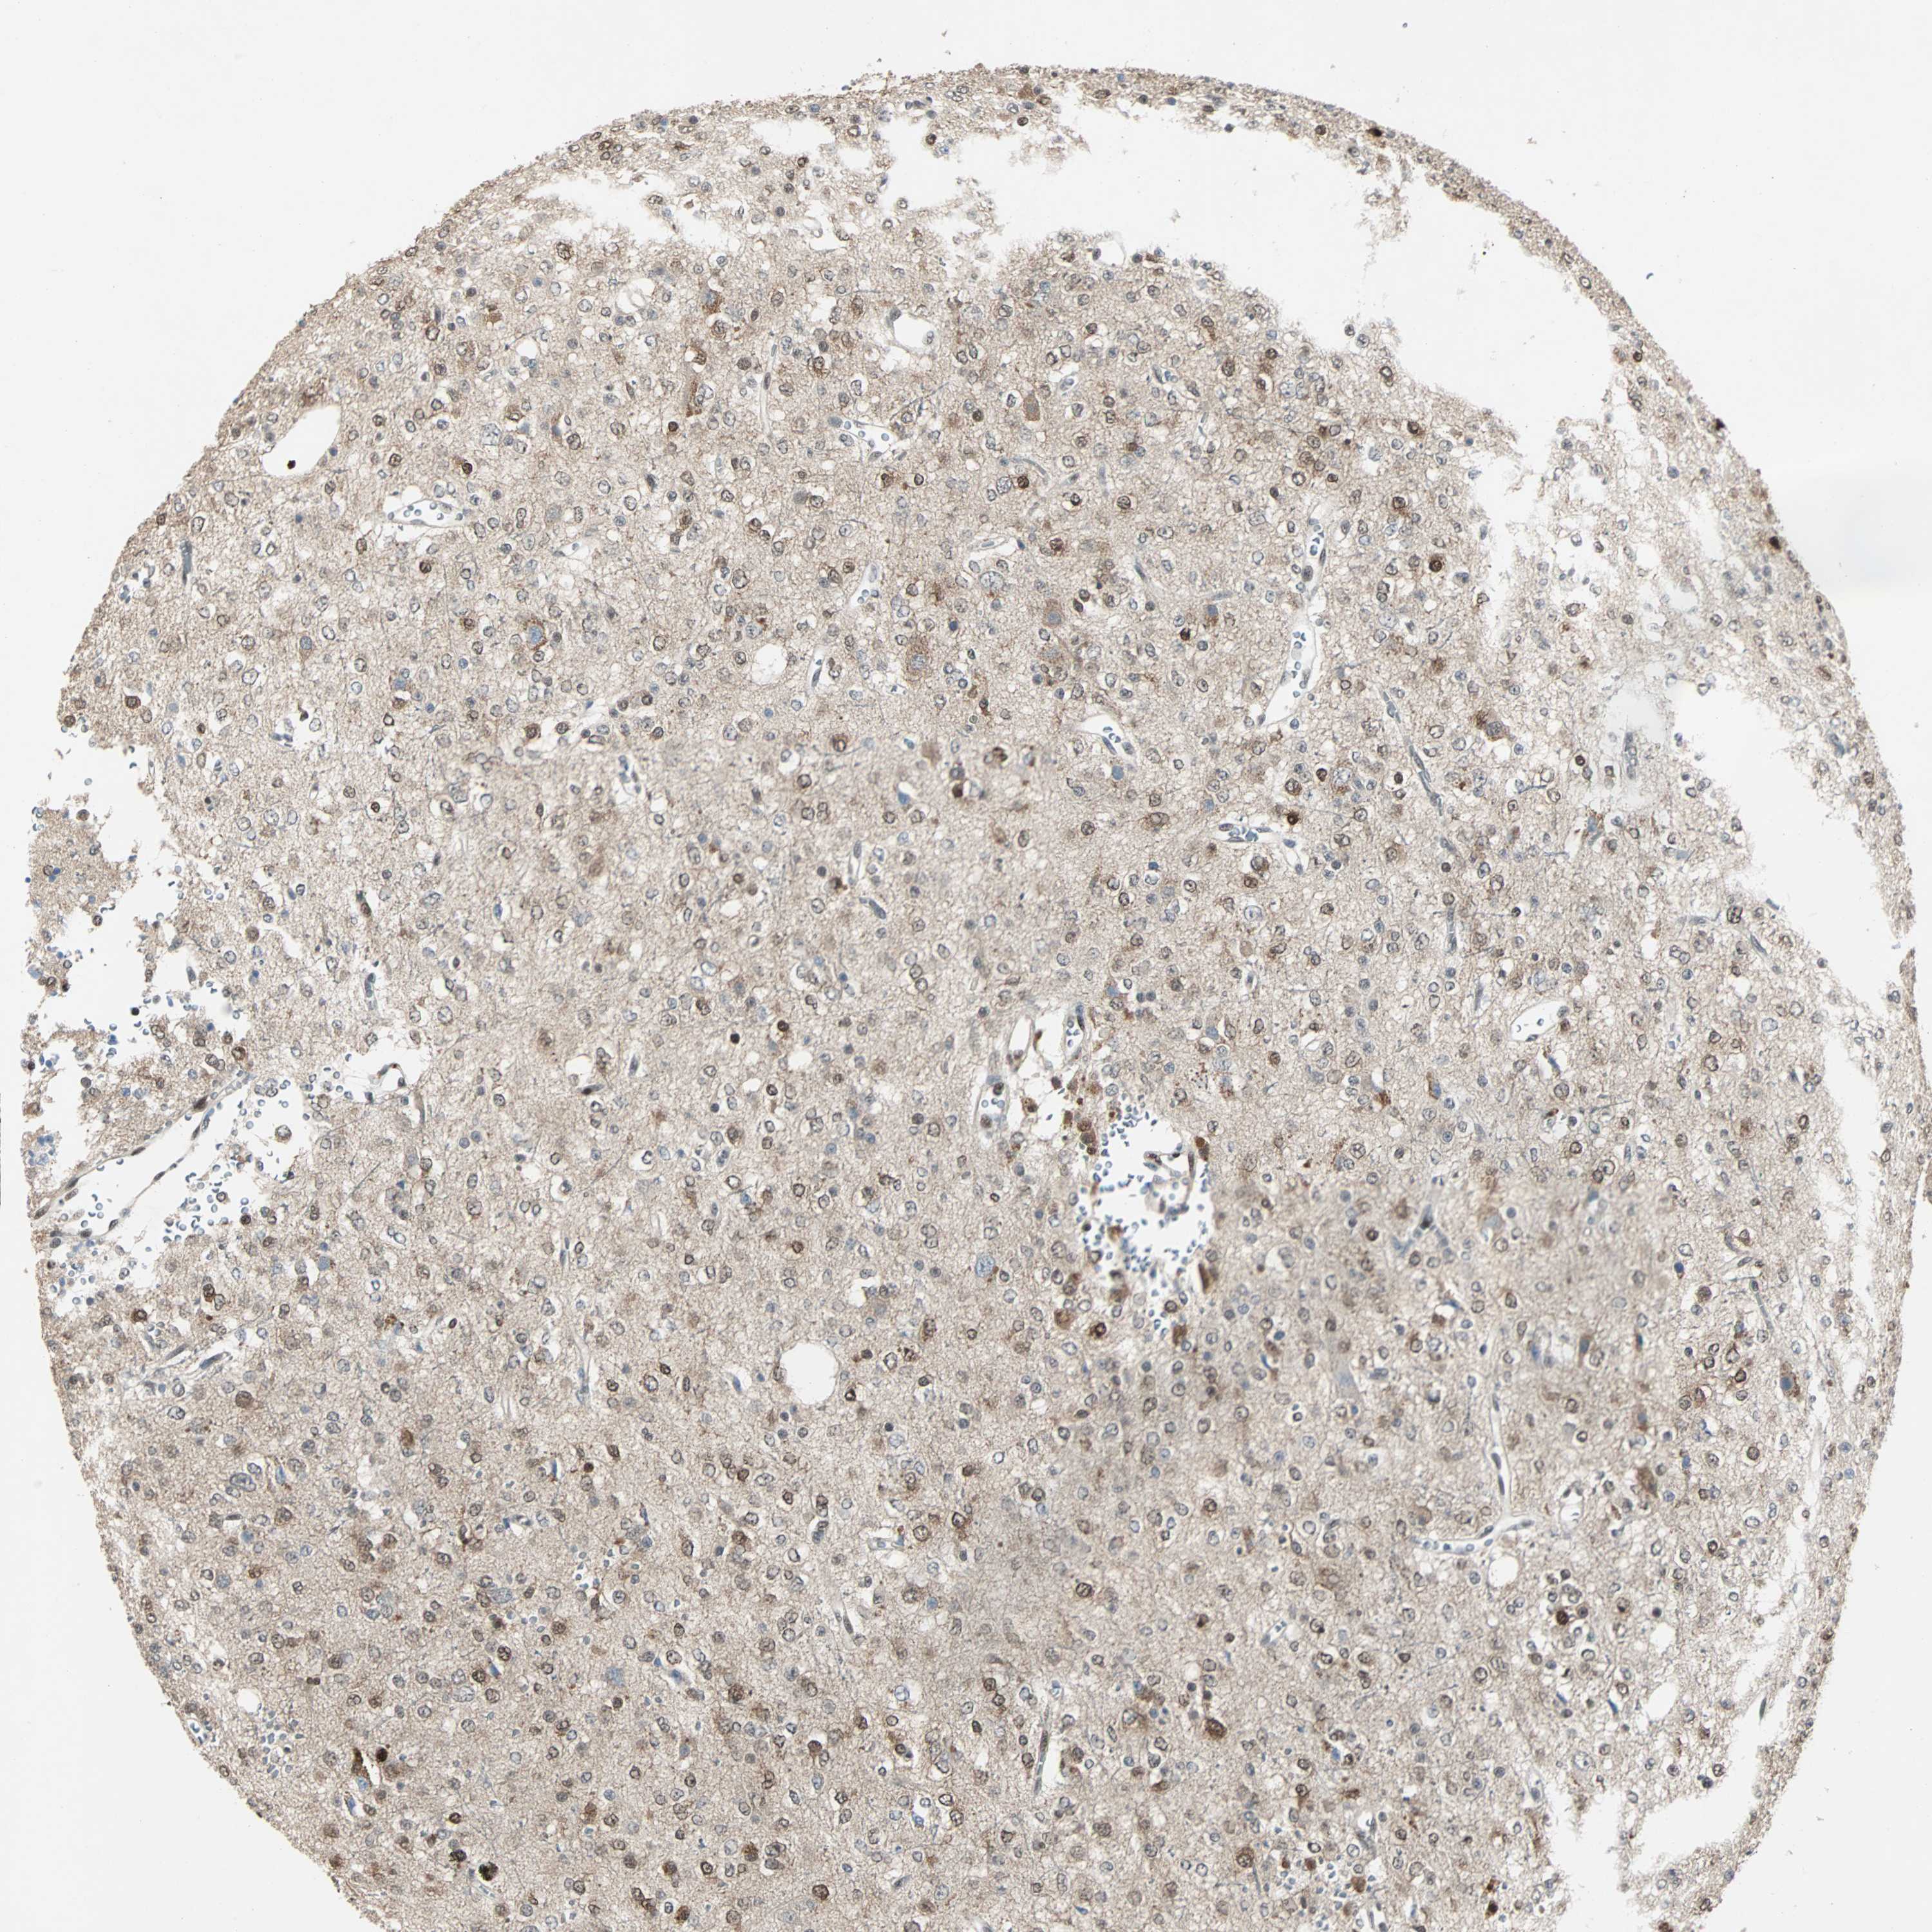

GLIOMA - Protein expressioni

A mouse-over function shows sample information and annotation data. Click on an image to view it in a full screen mode. Samples can be filtered based on level of antibody staining by selecting one or several of the following categories: high, medium, low and not detected. The assay and annotation is described here.

Note that samples used for immunohistochemistry by the Human Protein Atlas do not correspond to samples in the TCGA dataset.

Antibody stainingi

Antibody staining in the annotated cell types in the current human tissue is reported as not detected, low, medium, or high, based on conventional immunohistochemistry profiling in selected tissues. This score is based on the combination of the staining intensity and fraction of stained cells.

Each image is clickable and will lead to virtual microscopy that enables deeper exploration of all samples and also displays staining intensity scores, fraction scores and subcellular localization as well as patient and tissue information for each sample.

HPA022434

HPA022953

HPA022959

HPA028758

CAB007783

Glioma, malignant, High grade

Glioma, malignant, Low grade

Glioblastoma, NOS